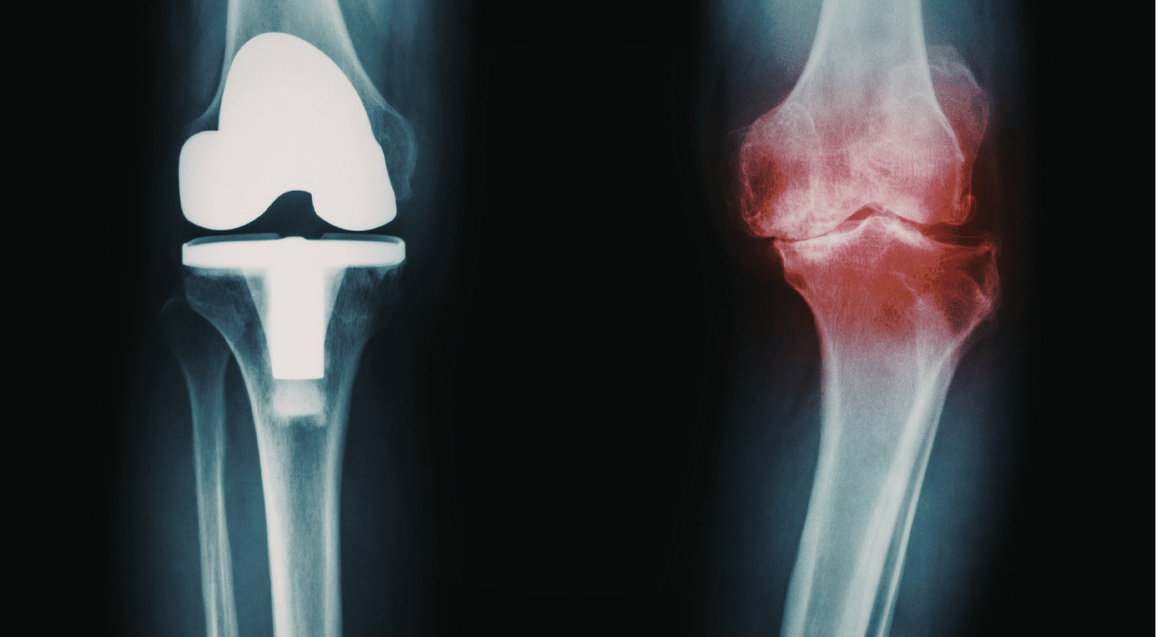

Knee Replacement Rehabilitation

Complete recovery program after total or partial knee replacement surgery.

Knee Replacement Rehabilitation in Indore

Knee replacement surgery gives you a new joint, but your muscles still need retraining. Thousands of patients in Indore undergo total knee replacement (TKR) every year. The difference between a good outcome and an excellent one often comes down to the quality of post operative physiotherapy.

Goals of knee replacement rehabilitation:

- Achieve full knee extension (straightening)

- Regain at least 120 degrees knee bending

- Strengthen quadriceps and hamstring muscles

- Walk without limp or support

- Climb stairs normally

Return to daily activities and light recreation